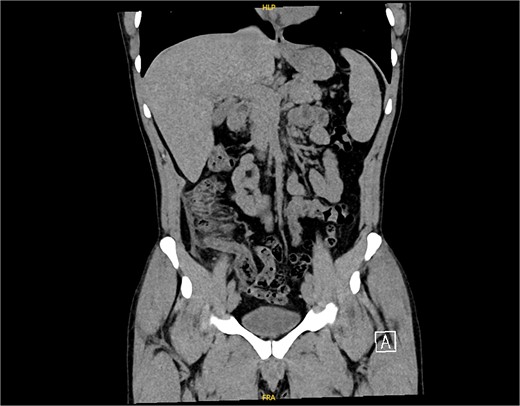

The non-contrast CT scan revealed a retrocecal appendix measuring 11 mm in diameter, with periappendiceal fluid and fat smudging, and reactive thickening of the cecum, indicating uncomplicated acute appendicitis. The patient was admitted to the surgical department and scheduled for a laparoscopic appendectomy (Figs 2 and 3).

CT scan picture with an axial view showing acute inflamed appendix with peri-appendicular fat smudging, confirming the radiological finding of acute appendicitis.